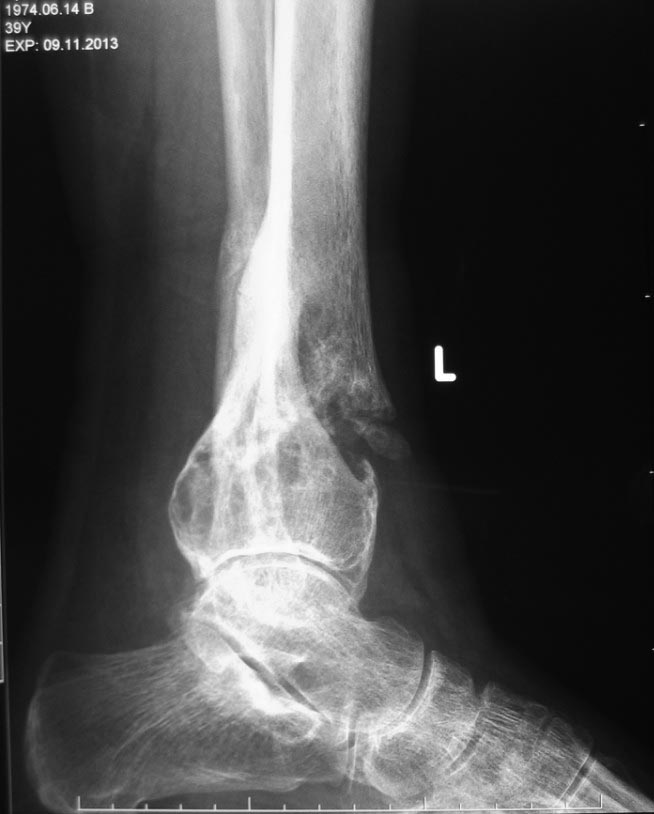

Здравствуйте, дорогие коллеги. Обратился мужчина около 50 лет. Примерно 20 лет назад оперирован по поводу остеобластокластомы. Жил вполне нормально. Год назад - открытый перелом голени (газонокосилка переехала), при рентгене обнаружен рецидив опухоли. Перелом сросся. Опухоль естественно осталась. Сейчас ходит с тростью для страховки и после перелома еще не восстановился. Вопрос по лечебной тактике. Спасибо С уважением Александр Артемьев

Случай очень необычный. Остеобластокластома в 50 лет, редкость, а рецидив через 30 лет, ещё большая редкость. Я бы сделал МРТ и биопсию, чтобы подтвердить, что это и правда рецидив остеобластокластомы а не метастаза или саркома. Если и вправду рецидив, то далее следовал бы по методике, описаной в этой статье: http://www.sarcoma.org/html_articles/cryo%20gct.htm.

Вкратце, кюретаж, обработка кости жидким азотом, а потом внутренняя фиксация и заполнение полости костным цементом. Между цементом и хрящом сустава следует сделать небольшую прослойку костного трансплантата из подвздошной кости, чтобы уменьшить вероятность артрита.

Если это действительно была гигагноклеточная опухоль, то рецидив вполне предсказуем. По снимкам не видно признаков малигнизации, но биобсию все равно делать нужно.

На второй рентгенограмме же дата рождения и возраст написаны. 39 лет, а не 50. Внимательнее же нужно быть:)